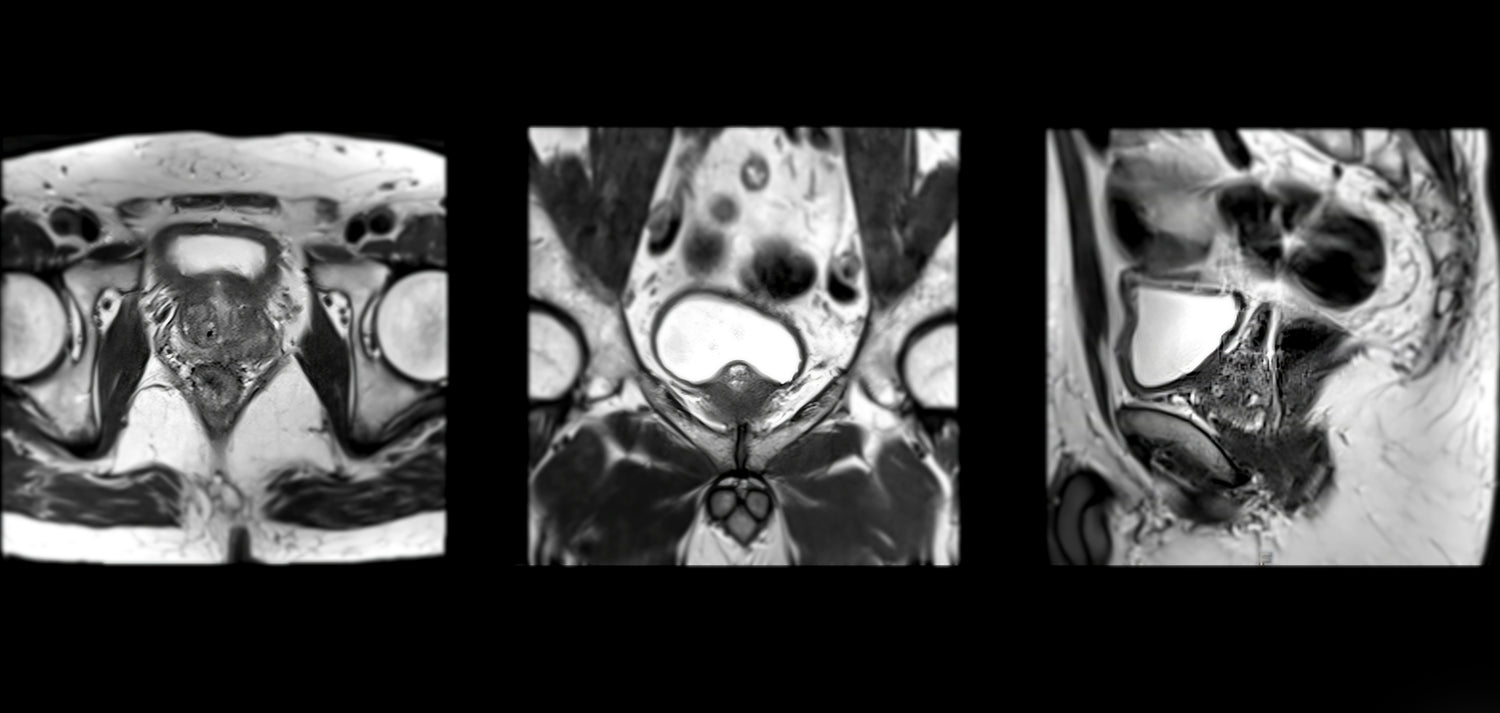

Rezonans magnetyczny (MRI) miednicy małej

to nowoczesne badanie obrazowe, które pozwala na szczegółową ocenę nerek, moczowodów, pęcherza moczowego oraz prostaty (u mężczyzn). Jest to metoda bezpieczna, ponieważ nie wykorzystuje promieniowania rentgenowskiego, a zamiast tego używa silnego pola magnetycznego i fal radiowych do uzyskania dokładnych obrazów narządów.

5. Tomografia komputerowa (TK) i rezonans magnetyczny (MRI)

📌 Zaawansowane badania obrazowe wykorzystywane w diagnostyce raka pęcherza.

• TK i MRI pozwalają ocenić, czy nowotwór rozprzestrzenił się na inne narządy.

• Pomagają określić stadium choroby i zaplanować leczenie.

Stosowane głównie w przypadkach już rozpoznanej choroby celem dokładnego zaplanowania zakresu leczenia.